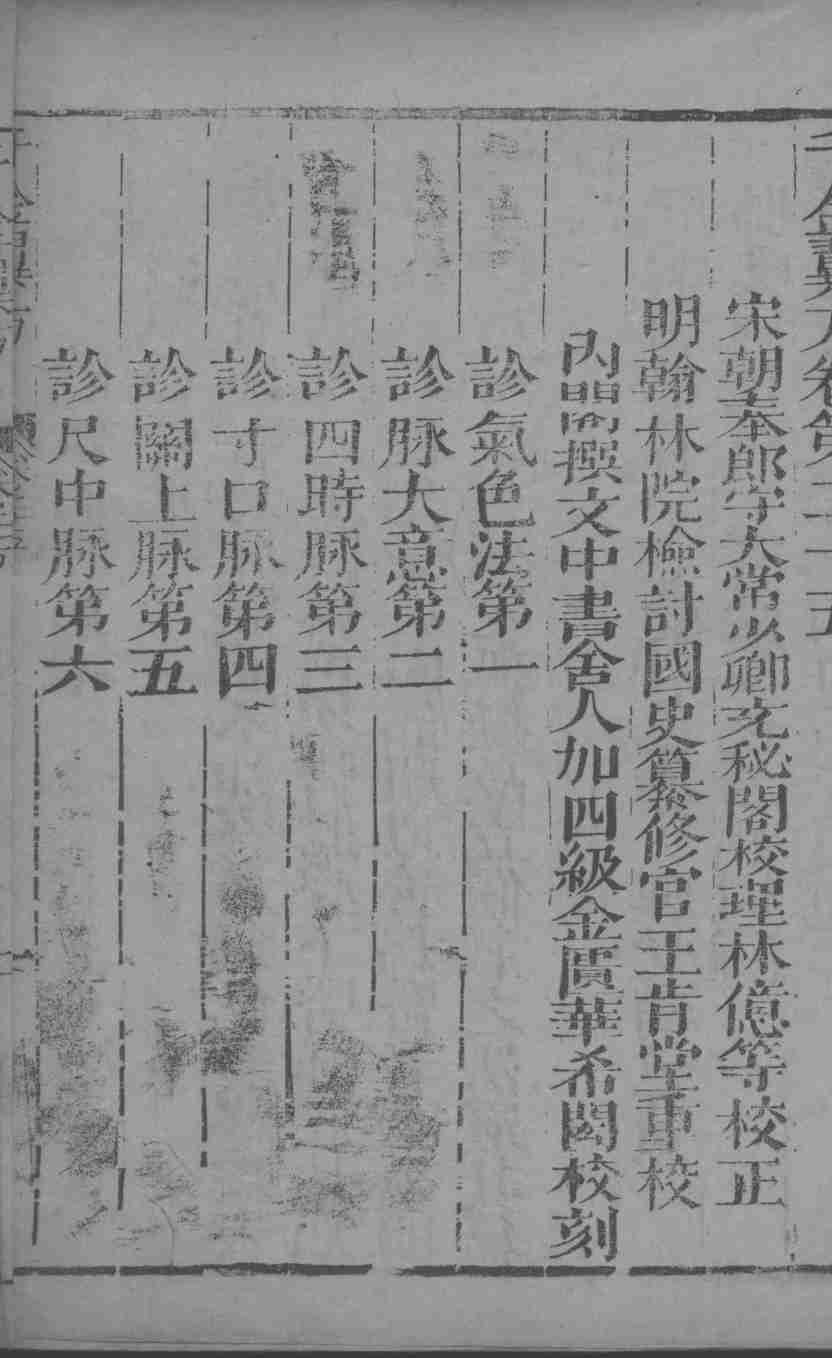

作者:不详

书籍分类:中医经典

书籍分类:中医经典